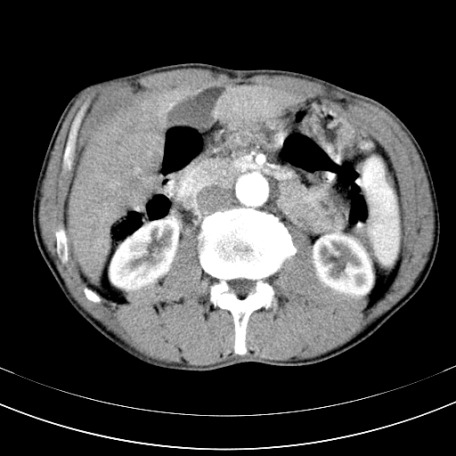

标题: CT21441:男55岁,上腹部胀痛半年余,请老师们看看是后腹膜淋巴

眼拙!仅见胰腺稍丰满,脾大。

腹主动脉右侧有一个,有肿瘤病史吗?

转移瘤或淋巴瘤

腹膜后淋巴结肿大,原因待查。